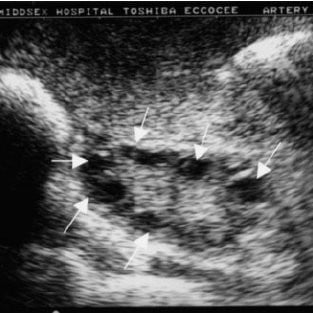

Let’s say you’re looking at an ultrasound of a PCOS patient, and there are cysts present. One or both ovaries will contain small, immature ovarian follicles. These follicles will show up in medical imaging as cysts.

With PCOS, ovarian follicles stay in an immature state because of abnormal hormone levels present in the person’s body. These follicles can't grow to their fully matured state where an egg would normally be released. Instead, the immature follicles accumulate in the person’s ovaries.

Some people have 12 or more cysts present in their ovaries. The good news is that the number of cysts you have tends to decrease with age. And, symptoms can often be improved through medical help and lifestyle adjustments.